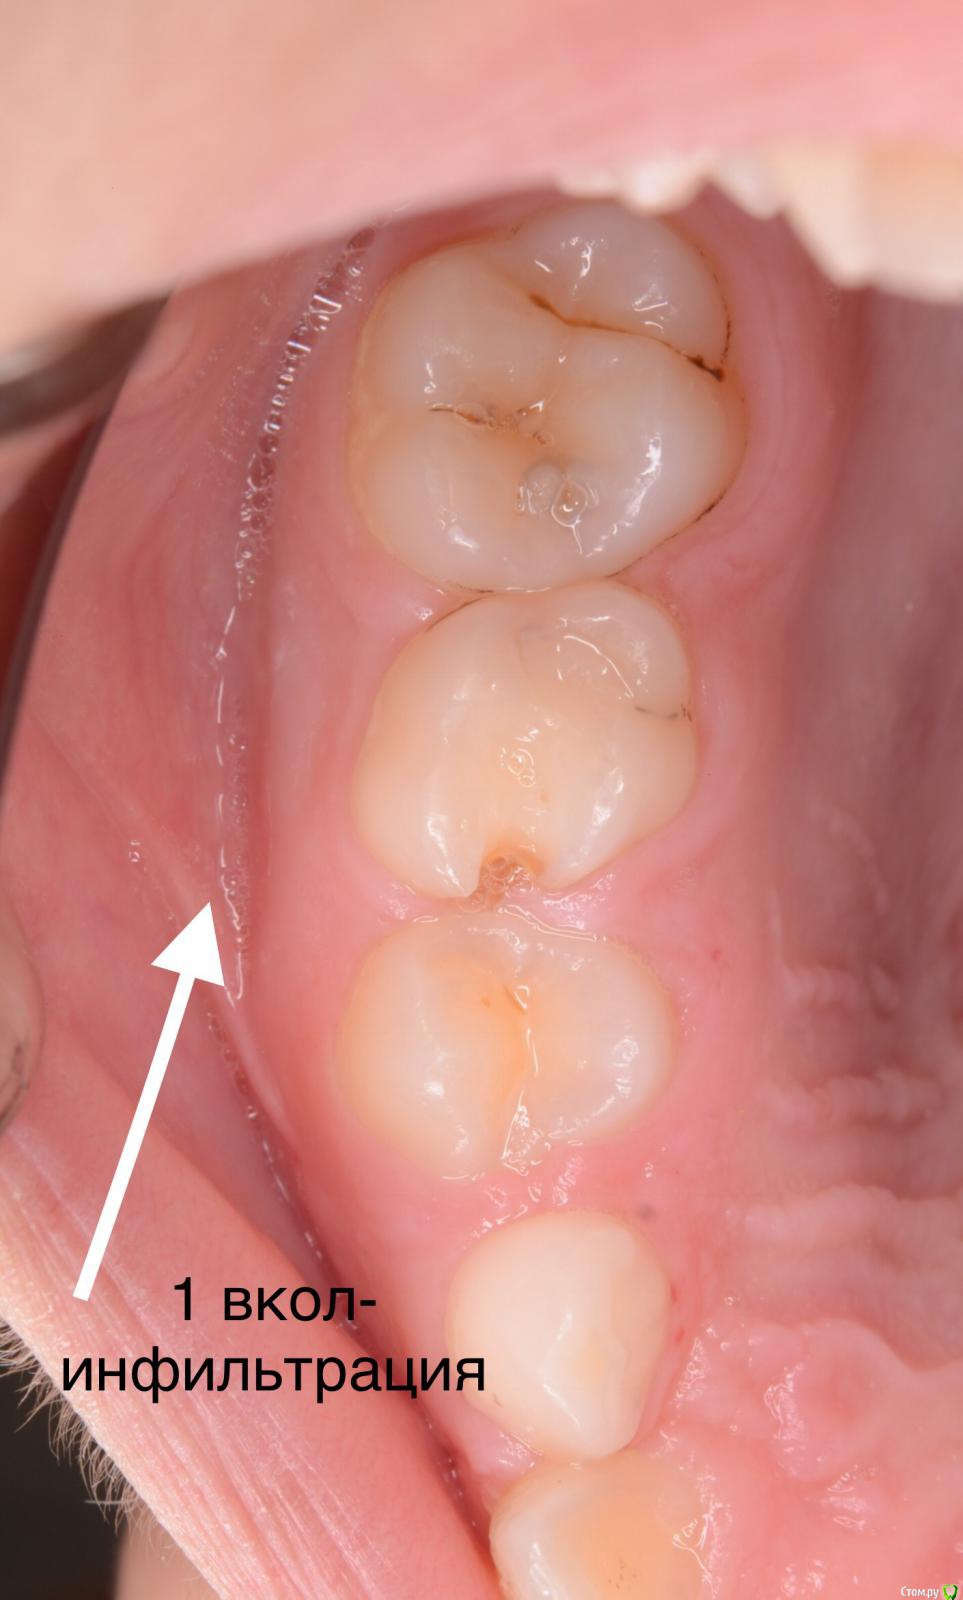

CRAZYDUCK Опубликовано 3 июня, 2018 Автор Поделиться Опубликовано 3 июня, 2018 (изменено) ]Так получается, что и на герметизацию изолируетесь? А как же им в этом случае анестезию там где кламп делаете или он такой что не давит? спасибо ! Анестезия здесь была проведена - лечили же кариес 7.4 зуба. Насчет анестезии - я практически всегда лечу с обезболиванием . Ведь постановка клампа, матрицы , клина неприятные процедуры. Анестезию делаю по книжке Даггала. Сначала инфильтрация , прижимаю создавшееся депо анестетика ватным валиком ненадолго и ввожу по сосочкам медиально и дистально от нужного зуба. На фото анестезия 5.5 зуба. Иголка 30 G 12 мм. После такой анестезии делаю проводниковую если нужно лечить верхние или нижние 6. На такую плавную анестезию уходит карпула, иногда полторы. Изменено 3 июня, 2018 пользователем CRAZYDUCK 1 Ссылка на комментарий

CRAZYDUCK Опубликовано 3 июня, 2018 Автор Поделиться Опубликовано 3 июня, 2018 Итак , фотки . Во время проведения по сосочкам ВАЖНО найти эту точку вкола , чтобы шло так , что на поршень давишь , но умеренно . Бывает вводишь в сосочек, давишь , а анестетик не идёт . А бывает , что наоборот выливается . Ищем другое место вкола , как правило выше ( на верхней челюсти ) и ниже ( на нижней )от первоначального вкола. Это с опытом прийдет . Например , 7.4 кариозная полость дистально и забита пищей , десна воспалена , если вводить в дистальный сосочек , то все будет выливаться из-за воспалённой десны. Нам важно получить побеление ( ишемию кольцевую) . У иглы есть срез . Мы можем после инфильтрации согнуть иглу срезом дистально или медиально . На примере 7.4 - срез иглы направляем дистально и колем в сосочек между 7.3 и 7.4 и десна белеет от клыка к четверке.десна белеет язычно внизу и небно вверху. Это дело практики , и это несложно совсем . 1 Ссылка на комментарий

CRAZYDUCK Опубликовано 3 июня, 2018 Автор Поделиться Опубликовано 3 июня, 2018 (изменено) Фото. Ватные валики рвём напополам и одеваем на иголку , чтобы ее не было видно ( валики проавтоклавированы );перед герметизацией стараюсь одевать коффердам , безболезненно пока одевать не умею , поэтому сначала делаю анестезию . Я перед герметизацией чищу глицином ( каво профифлекс , и ещё рондофлексом могу пройтись 27 мкм оксид алюминия , а без платка - ощущения неприятные Изменено 3 июня, 2018 пользователем CRAZYDUCK 3 Ссылка на комментарий